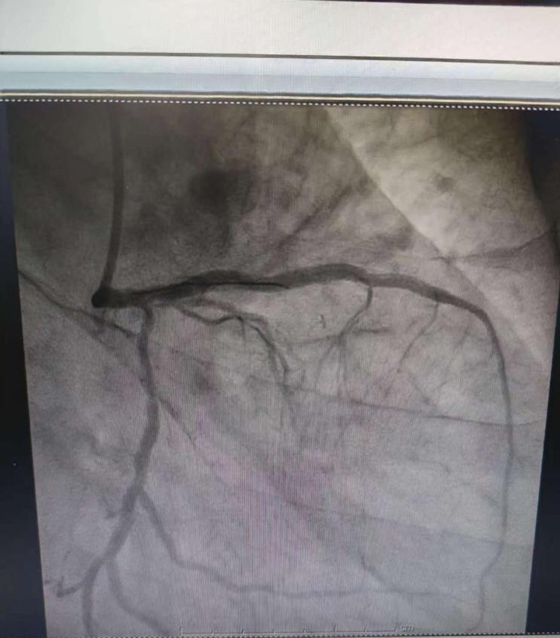

完善术前准备后,心血管内科主任彭道地、主任医师范爱德携手心脏介入团队经过长达数小时的手术时间,经过导丝反复尝试找到前降支血管真腔,严格按照PSP原则,于前降支及回旋支狭窄病变处植入药物洗脱支架覆盖病变。手术治疗过程顺利,没有出现夹层及冠脉穿孔等并发症。术后复查造影显示支架贴壁良好,支架内无狭窄,远端血流正常,手术顺利完成。术后病情平稳,顺利出院。择期行右冠PCI术。

术后造影